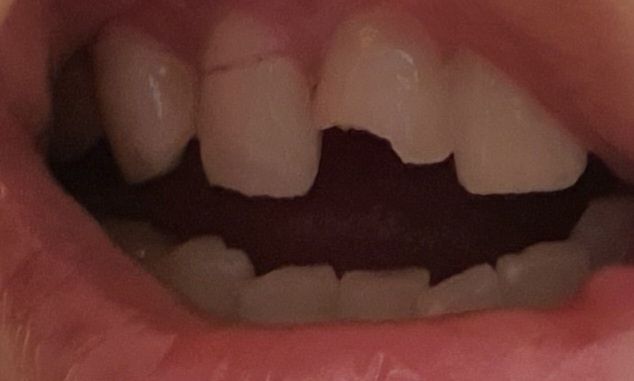

넘어져 앞니와 그 옆에 이가 깨졌는데 앞니는 신경치료 크라운 옆니는 임플란트 해야 한다는데 이빨 살릴 방법 없을까요..? 앞니는 신경이 일부 노출되었고 옆니는 뿌리부근이 부러졌어요.

• 2번 째 사진

• 안녕하세요 치과의사 김철진입니다. 사진상에서 왼쪽 치아는 치아의 머리가 많이 깨져서 발치후 임플란트를 해야될것같고 오른쪽 앞니는 신경치료를 해서 살려 볼것같습니다.

• 기존에 답변드렸듯이 앞니는 신경 치료후에 크라운으로 가능하나, 이미 뿌리가 손상이 입은 옆니는 발치가 필요로 되며, 임플란트 치료가 필요로 됩니다. 보다 정확한 상태 확인을 위해 치과 진료를 받고 치료 방향을 결정하길 권합니다.